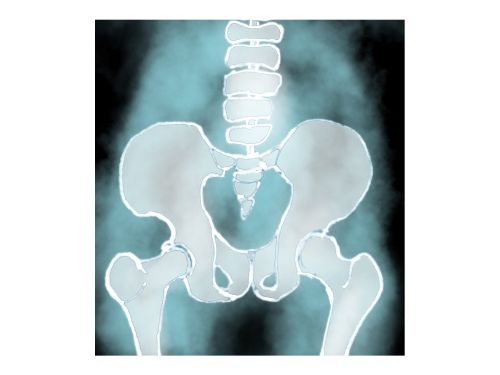

仙腸関節とは、仙骨(骨盤内にある大きな骨)と腸骨の間にある関節のことです。上半身と下半身のつなぎ目という、重要な役割を担っています。関節は緩みすぎてもいけないし、硬くなりすぎてもダメです。バランスに偏りが出ることで痛みが発生してしまいます。

レントゲン画像では、仙腸関節のズレは映りにくいが骨盤の変位は確認できる。つまり仙腸関節は動くということです。

人間は二本足です。上体の全重量を仙腸関節(骨盤)で受け止めます。骨盤が歪めば背骨や脚にも影響が出る。